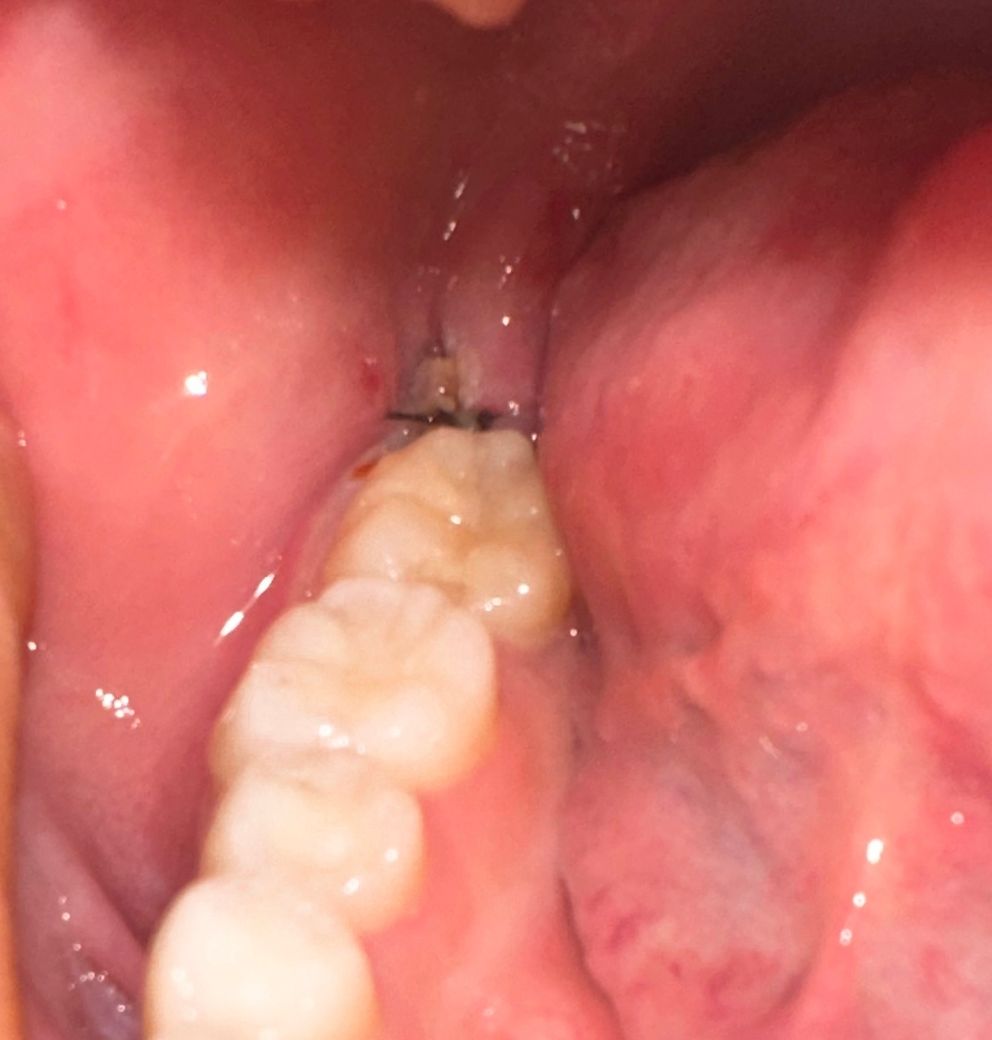

12일 오전에 발치한 매복사랑니 사진입니다

어제까진 괜찮았던거 같은데 오늘 밥 먹고 보니까 잇몸 사이 구멍에 저런게 있어요ㅠㅠ 음식물인거 같기도 한데.. 설마 드라이소켓은 아니겠죠? 색깔이 너무 불길해서 올려봅니다. 살짝 웃을때나 입 크게 벌릴 때 실이 땡기듯 아파요ㅜㅜ

물가글하고 헥사메딘 했는데도 안 빠져요..!

정상적으로 아물고 있는 것이 입니다. 그냥두면 됩니다. 원래 구멍이 생기고 하얗게 딱지가 앉은 것이니 정상입니다.

발치를 하고나서 잇몸이 치유되는 과정중에 생기는 자연스러운 현상이니 너무 걱정은 안하셔도 될것같습니다.

음식물이 끼인 것으로 보입니다. 억지로 제거하실 필요는 없고 드라이소켓처럼 보이진 않습니다.

드라이소켓 양상은 아니니 걱정 안하셔도 됩니다 발치 후 주의사항 잘 지켜주시고 해당부위는 약한 양치질, 물가글 통해서 자극안가게 조심스럽게 음식물뻬주시기 바랍니다